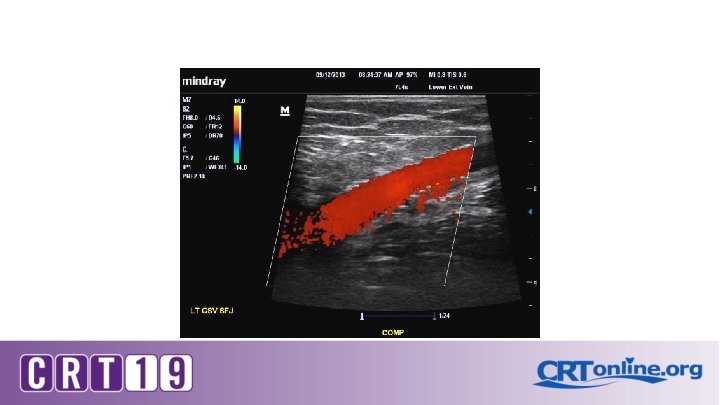

Patient position Erect, semi-erect or reverse Trendelenburg Proximal compression (or Valsalva) to elicit reflux for thigh veins Calf compression of distal veins Flow reversal duration

On Ultrasound: Grey scale , color and Doppler Compressibility Phasic flow Augmentation Perforators Reflux and its duration Vein diameters

Diagnostic testing for Venous insufficiency CVI Venous Doppler *technique* S. V. reflux >3 secs Stasis ulcer Stasis dermatitis S. V. reflux >3 secs Deep vein reflux No reflux Vein diameter Symptoms Compression stockings Ablation